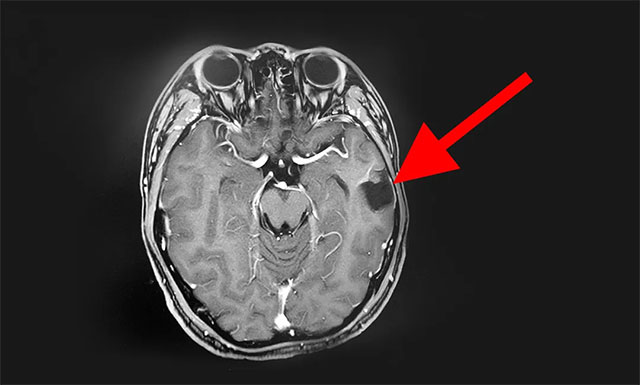

術(shù)后,患者病理標(biāo)本檢驗(yàn)結(jié)果為:海綿狀血管瘤。經(jīng)過一周多時(shí)間的康復(fù)治療,患者恢復(fù)良好,其癲癇癥狀未再發(fā)作,家人總算放心了,再過幾天后晨晨就可以出院了,但因晨晨體質(zhì)較瘦弱,張先生想讓兒子在醫(yī)院多康復(fù)治療一段時(shí)間再出院。

▲ 術(shù)后影像結(jié)果顯示:患者海綿狀血管瘤已切除